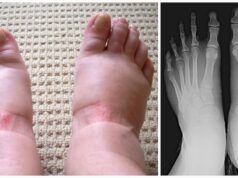

Swollen feet and hands: 10 alarming warning signs you should never ignore

When you have swollen feet, most people will probably think you’re pregnant, injured, or have a job where you stand up all day.

But the...